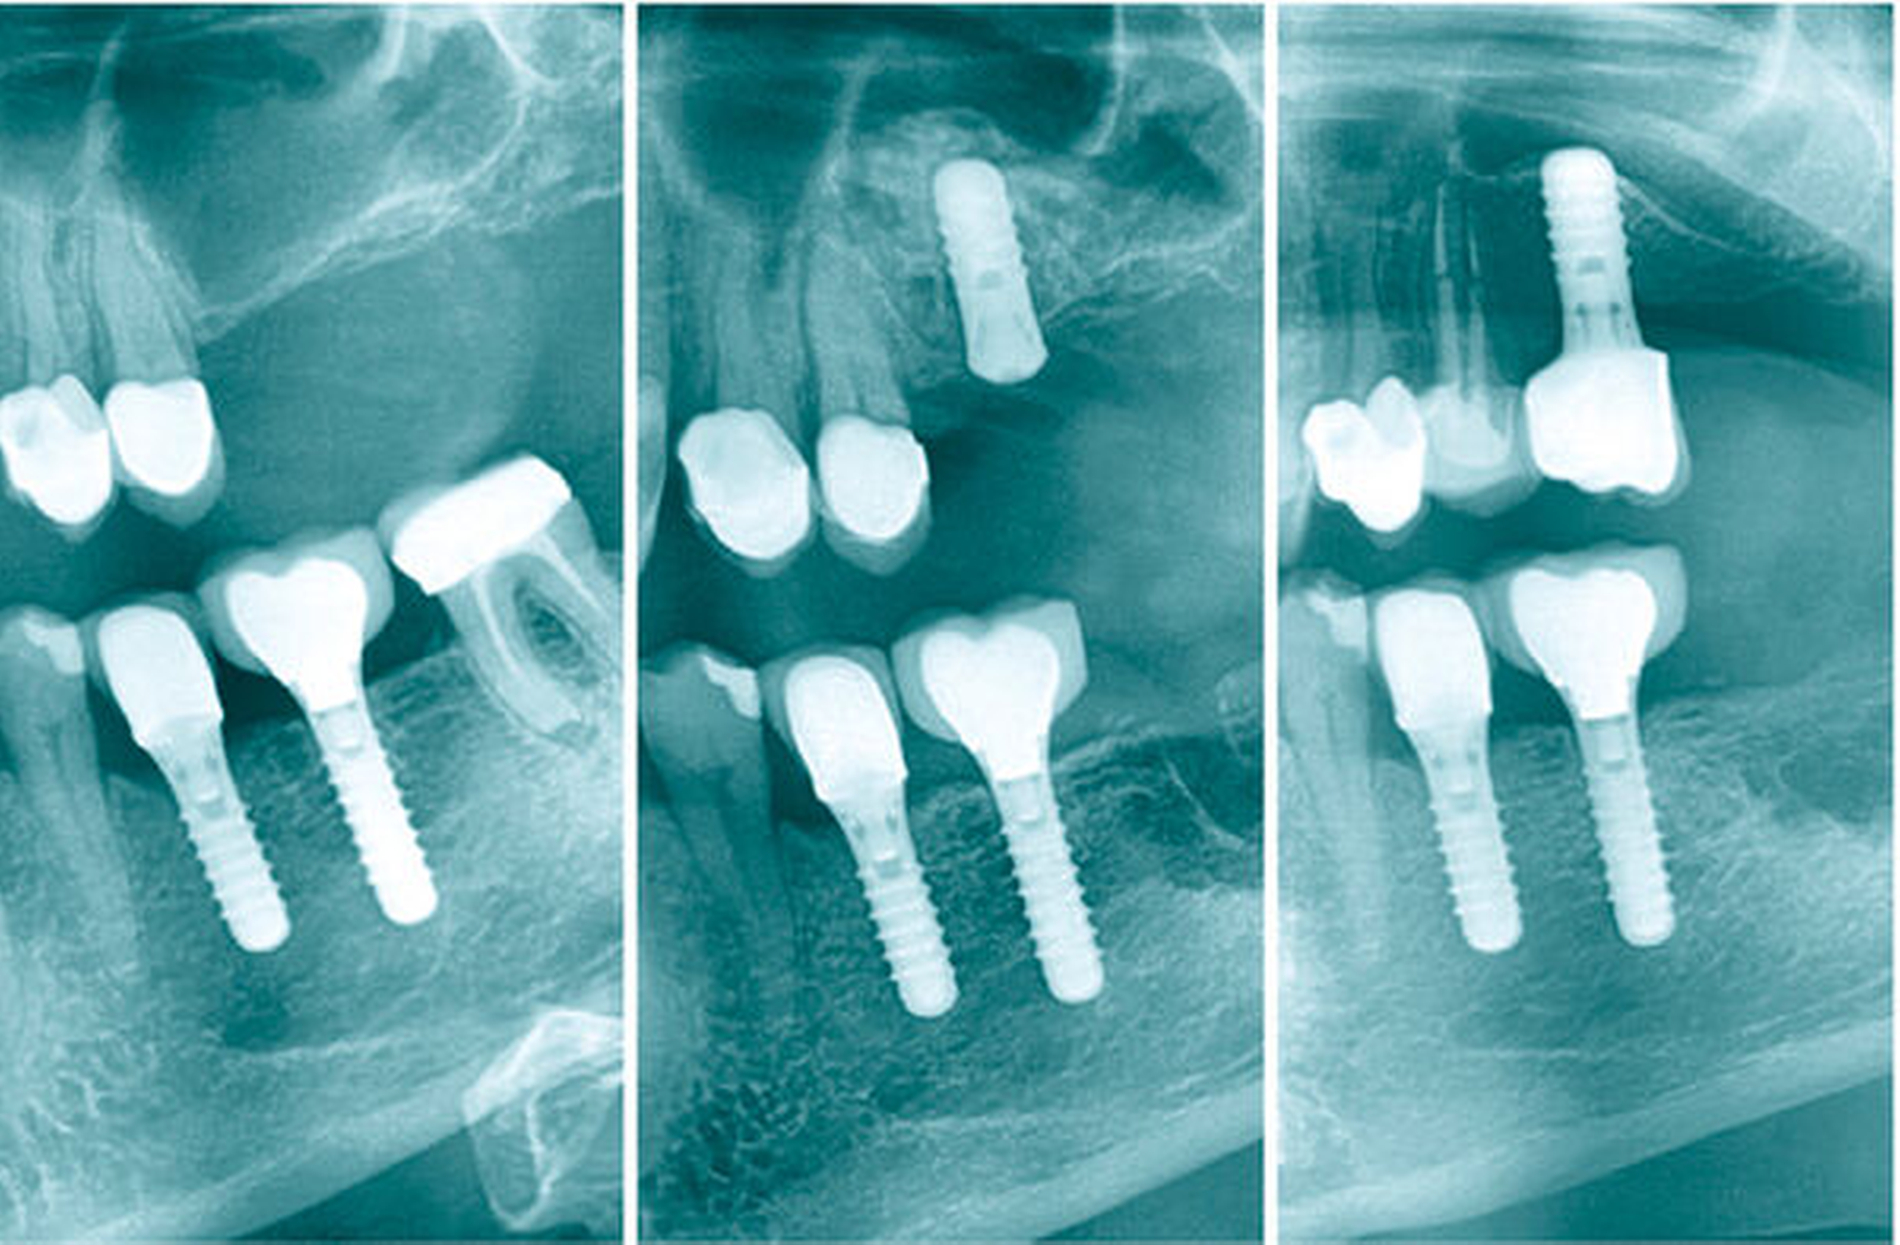

In den Abbildungen 6 bis 9 sind mehrere Fälle mit langem Beobachtungszeitraum dargestellt. Beachtenswert ist vor allem der zu beobachtende vollständige Umbau des Knochens inklusive der Ausbildung einer neuen Kompakta. Die augmentierten Bereiche sind nach wenigen Jahren nicht mehr als solche zu erkennen. Die Arbeit mit autologem Knochen ist insbesondere für die Patientengruppe interessant, die bevorzugt nach biologisch sicher verträglichen Behandlungen sucht. Dieser Trend nimmt unseren Beobachtungen nach stetig zu. n

In unserer Praxis werden beim externen Sinuslift im allergrößten Teil der Fälle Tissue-Level-Implantate verwendet. Der Hauptgrund ist die wissenschaftlich belegte überdurchschnittliche Periimplantitisresistenz [Derks et al., 2015; Buser et al., 2012; Buser et al., 1999; van Velzen et al., 2015]. Zusätzlich kann der tulpenförmige Implantathals bei Knochenangeboten von weniger als 1 mm vor einer Luxation des Implantats in die Kieferhöhle schützen.

In OPGs von Fällen, in denen rein autolog transplantiert wurde, fällt unter Umständen eine Sinterung des Knochens um die Implantatspitze auf. Eine frühe Belastung der Implantate kann diesem Vorgang entgegenwirken. Die Hauptbelastung beim Kauvorgang trägt bekannterweise der Knochen im koronalen Drittel des Implantats, der Druck lässt Richtung apikal immer mehr nach [Himmlová et al., 2004]. An der Implantatspitze erfährt der Knochen unter Umständen dann keinerlei Belastung mehr und atrophiert dementsprechend, was jedoch zu keiner Verschlechterung der Prognose führt. Betont werden muss, dass diese „Inaktivitätsatrophie“ unsere persönliche Hypothese ist. Auch in der Literatur konnte allerdings bisher kein negativer Effekt auf die Implantatüberlebensrate festgestellt werden [Chen et al., 2021]. Unsere Erfahrung zeigt, dass dieser Effekt ab einer Implantatlänge über 10 mm signifikant zunimmt, so dass wir inzwischen nur Implantate mit einer maximalen Länge von 10 mm verwenden.